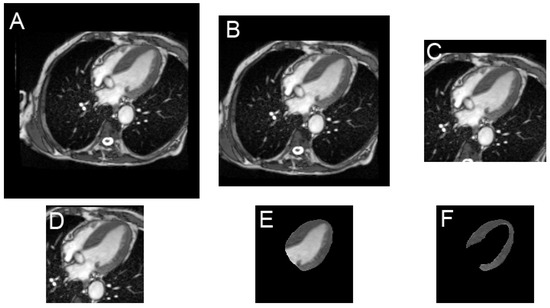

2.2. Image Preparation

2.3. Deep Learning Process